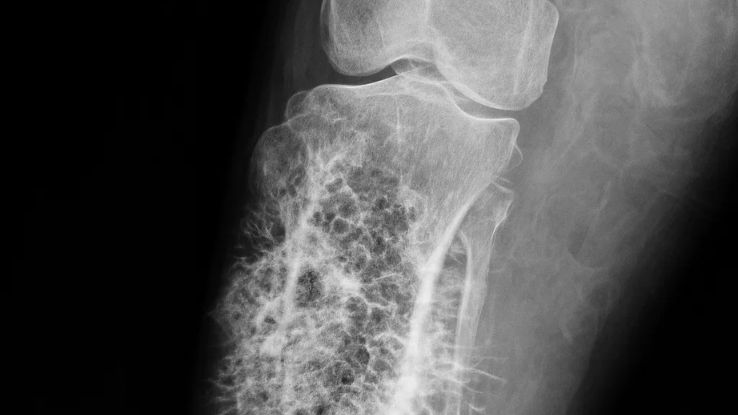

Para diagnosticar el cáncer de hueso, el médico puede solicitar estudios de imagen como radiografías, resonancia magnética o tomografía, además de análisis específicos.

En algunos casos, es necesario realizar una biopsia para confirmar el diagnóstico y determinar el tipo de tumor que se encuentra en el hueso. El tratamiento depende del tipo de cáncer, su ubicación y el estado general del paciente.